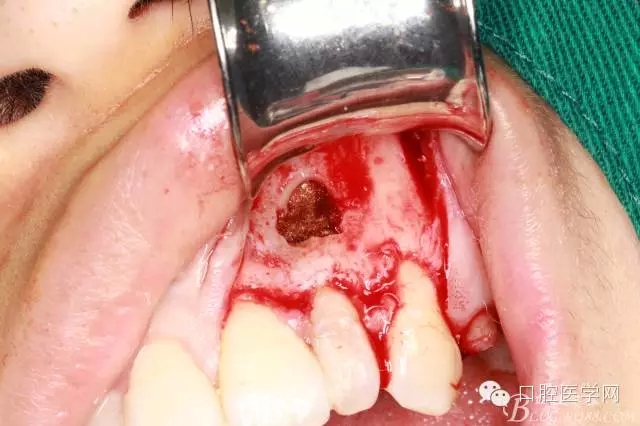

根切后可見開窗處清理干凈

刮出囊腫及牙根2.5MM

填明膠海棉(建議植骨和應(yīng)用生物膜)患者不同意因費用較高

復(fù)位縫合

填塞牙周塞治劑